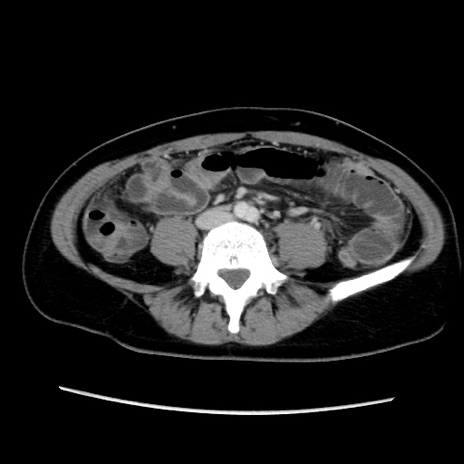

症例39(横断像)

【症例】40歳代女性

【主訴】上下腹部痛

【現病歴】2日目から下腹部痛あり。夜間は痛みで眠れなかった。昨日より上腹部痛と下痢が出現。臥位で痛みは軽快したため、休んでいた。本日になって臥位でも立位でも痛みが強くなってきたため救急要請。

【既往歴】子宮内膜症

【身体所見】部:平坦・軟、左上下腹部に圧痛あり、反跳痛あり。

【データ】WBC 21800、CRP 26.78